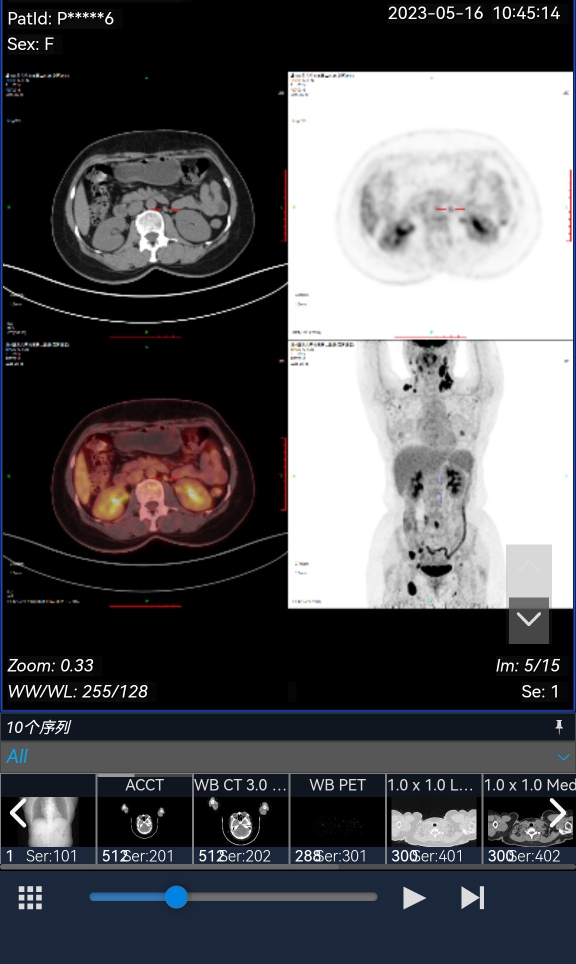

滤泡淋巴瘤转化而来的弥漫大b淋巴瘤,一般不一线做自体移植。除非是巨大包块型且化疗后有残余,需要自体移植延长复发时间。

这类亚型,就算做了自体移植,未来若干年还是有概率复发。只是有人复发成滤泡淋巴瘤。

根据你的疗效,不太考虑一线做自体移植。